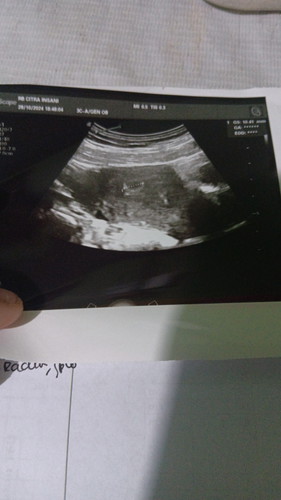

Hamil 6week

Apakah normal hamil 6week baru terlihat kantung?

sama bunda , saya hari minggu kemarin usg hasilnya masih kantong . kalo sesuai hpht 10 September sih udah 6week

kantongnya berapa cm itu Bun nanya saja 🙏

10,44mm

normal bund usg 2 minggu lagi